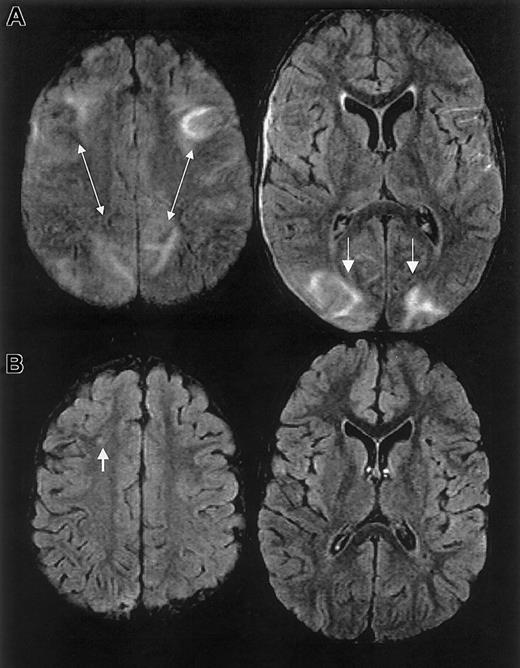

The initial clinical reading of the MRI, 1 day following endotracheal extubation, was bilateral ischemic infarcts and biparietal hemorrhages. The subsequent research reading of the initial MRI and follow-up MRI at 1 month and 15 months following discharge revealed findings consistent with RPLS complicated by hemorrhage; there was no evidence of infarction (Figure 3).

MRI findings for case 3.

(A) Extensive areas of FLAIR T2-weighted signal hyperintensity in the subcortical white matter and overlying gray matter of the posterior, frontal, and occipital lobes. Parenchymal hemorrhage was seen in the high parietal region predominantly on the patients's left. (B-C) Follow-up MRI scan 1 month and 15 months following discharge showed progressive evolution and resolution of the T2 signal hyperintensities with residual encephalomalacia in the left parietal region. These findings were consistent with reversible posterior leukoencephalopathy complicated by hemorrhage; there was no evidence of infarction.